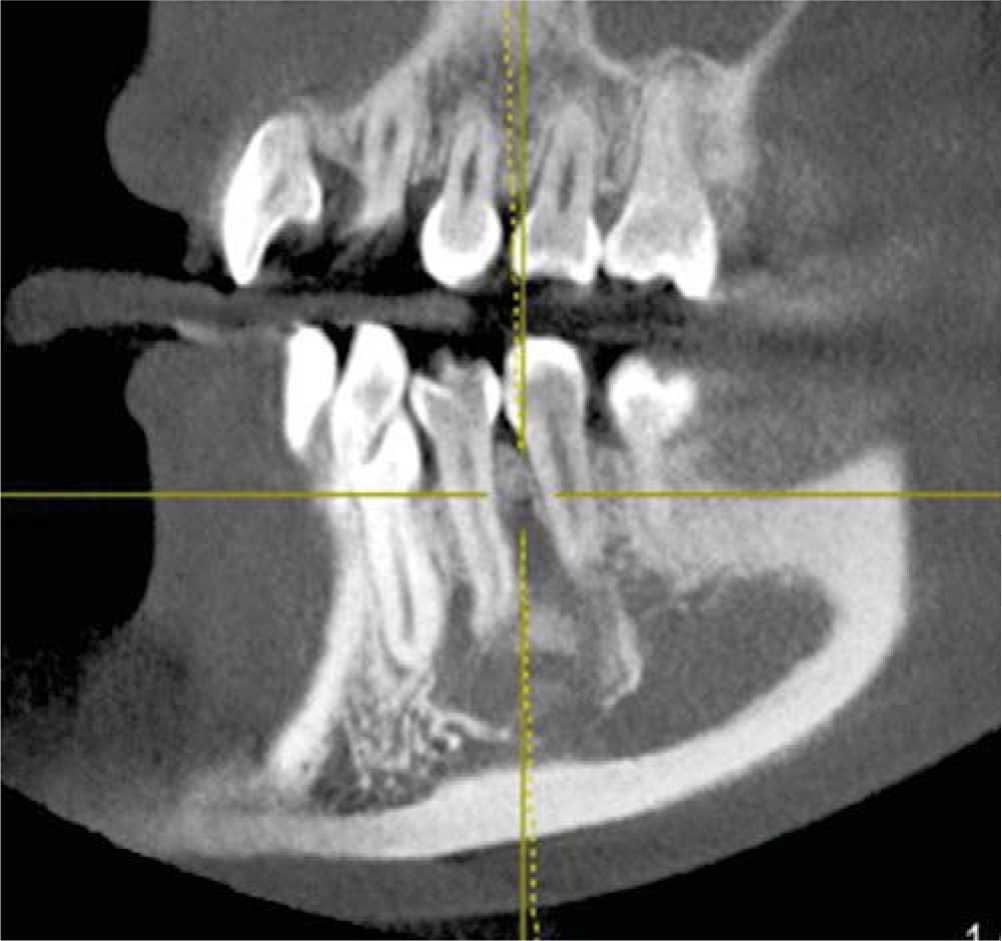

Orthopantomography revealed a radio-lucid lesion, with an irregular border and radio-opaque halo. The lesion involved first premolar, second premolar, and lower left canine, no root resorption or displacement was observed. The lesion exhibited a festooned border in the area of involved dental roots (Figures 2 and 3) and did not present expansion of cortical bone, nevertheless it exhibited thinning in lingual and vestibular cortical bone (Figure 4).

Figure 4 Cross-sectioned cut of the lesion showing thinning of lingual and vestibular cortical bone, without exhibiting expansion.

The lesion extended along the mandibular body without causing bone expansion; lower buccal and lingual cortical bone became thinner (Figure 4). There was no displacement of adjacent teeth towards the lesion; teeth responded positively to vitality tests. These data concur with those reported by Chrcanovic's30 and Xanthinaki's11 clinical case studies. Microscopic study revealed trabecular bone lacking significant histological data, such as mentioned by Harnet et al.9